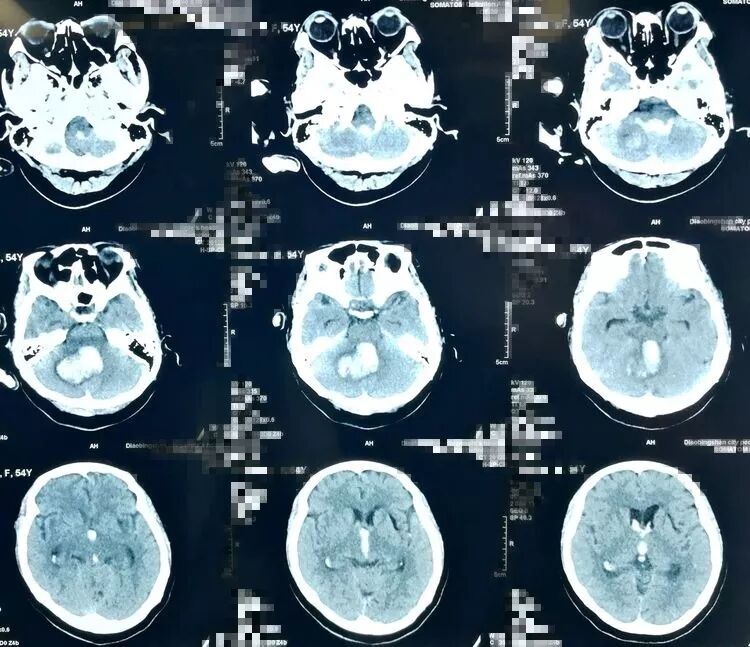

突发头痛2小时入院。既往高血压病史多年。入院后意识障碍逐渐加深,自主呼吸,节律不整齐,瞳孔正常大小。CT显示小脑蚓深部大量脑内血肿,IV脑室积血塑形,III脑室及侧脑室内积血。

术后病人意识水平明显改善,刺激睁眼,双侧肢体自主活动。复查头CT显示小脑血肿清除满意。